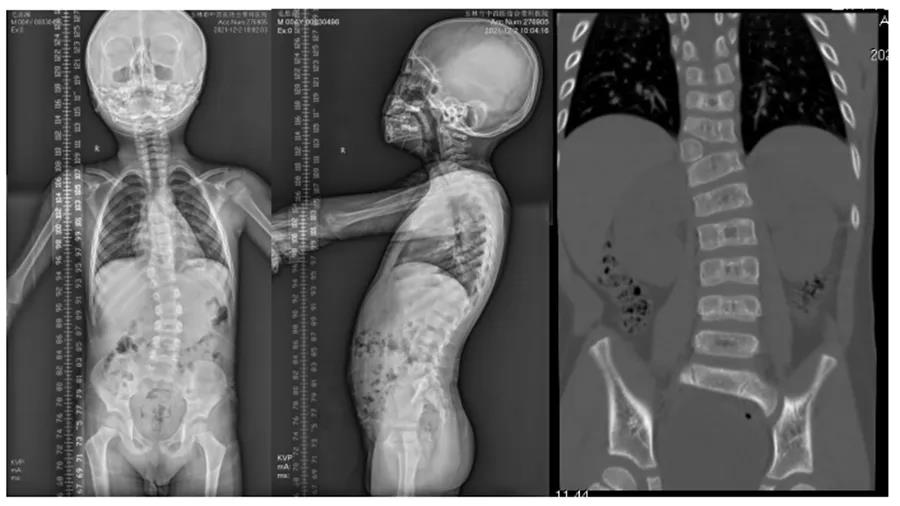

术前影像资料显示患儿胸11半椎体畸形

在脊柱二科陈涛主任的主持下讨论该患者的诊断及治疗方案,最后决定行胸11半椎体切除,钉棒上下短节段固定矫形。手术在陈涛主任及李嘉坤副主任带领下开展,手术中将胸11半椎体完全摘除,上下各用两枚椎弓根螺钉固定矫正侧弯畸形,手术历时2小时,出血约100ml,手术全程使用脊髓电生理监测,患儿手术全程监测运动、感觉电波正常。术后患儿双下肢肌力、感觉正常,复查影像学提示脊柱序列恢复正常,脊柱恢复“正直”。患者术后6天即可戴支具保护下床行走功能锻炼。

术后患儿影像资料,半椎体已完全切除,脊柱椎体序列恢复正常,脊柱恢复“正直”